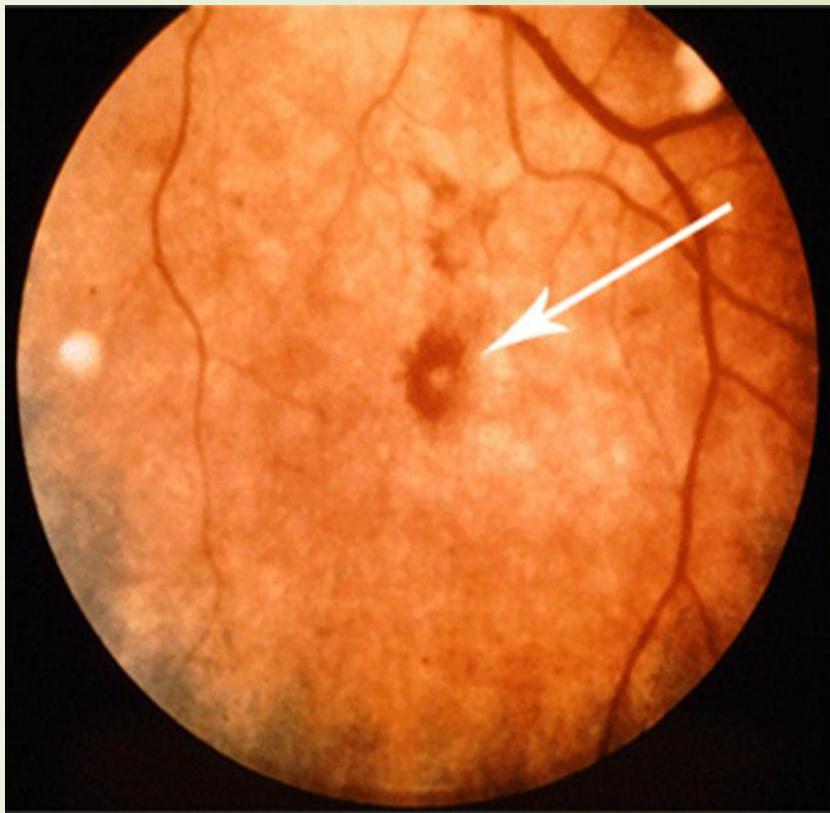

Roth Spots Retinal hemorrhages that have white/pale centers.

- Janeway lesions, Osler nodes, and Roth spots.

- Immune phenomena: Osler node, Roth spot, or glomerulonephritis.